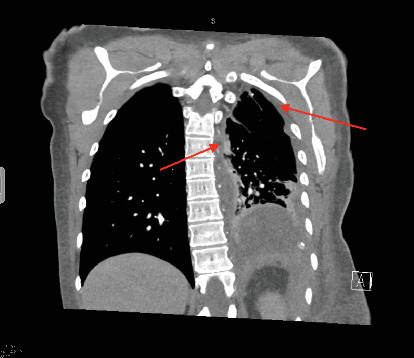

Epithelioid hemangioendothelioma (EHE) is an extremely rare vascular sarcoma that can initially present with a myriad of symptoms anywhere in the body. Imaging findings are often nonspecific, and the pathology tends to have overlap with other malignancies. As a result, it can be quite difficult to suspect and diagnose EHE. We present a case of pulmonary EHE in a 41-year-old female with left pleural thickening and subclavian tumor thrombus who was initially misdiagnosed and treated as mesothelioma. This instance demonstrates the importance of maintaining a broad differential and the utilization of repeat biopsies and next-generation sequencing for questionable diagnoses of atypical malignancies.

Abstract Image